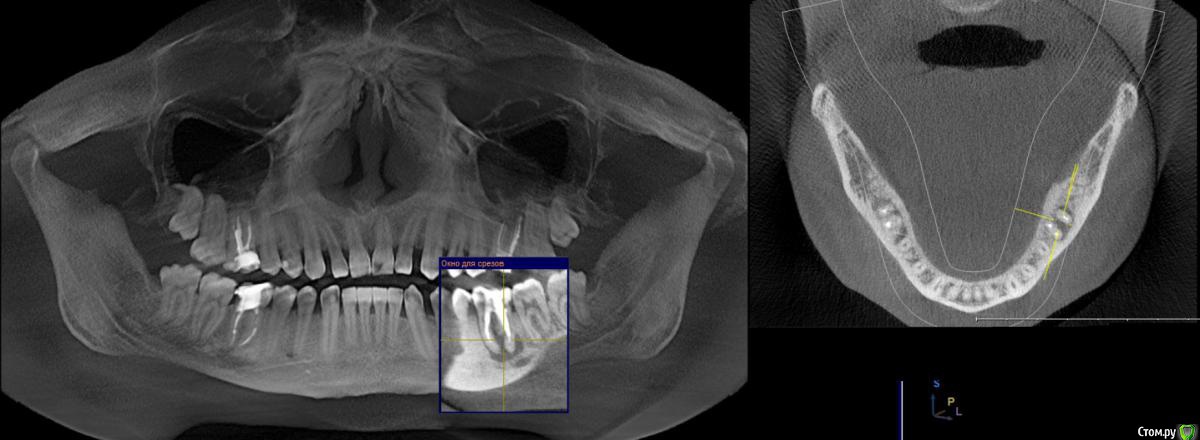

WHITE_ANTONIO Опубликовано 7 декабря, 2015 Автор Поделиться Опубликовано 7 декабря, 2015 Добрый вечер, прикладываю скриншоты КТ Ссылка на комментарий

DmitrySH Опубликовано 7 декабря, 2015 Поделиться Опубликовано 7 декабря, 2015 Прицельный снимки еще будут нужны, в хорошем качестве.26 - ничего особого не видно, просто периодонтит36 - перерасширены каналы, возможно наличие трещины или перфорации.16,46 - тоже требуют лечения Ссылка на комментарий

DmitrySH Опубликовано 7 декабря, 2015 Поделиться Опубликовано 7 декабря, 2015 (изменено) на основании данного снимка судьба зуба 36 под вопросом,а 26 - непонятно, но пока не увидел ничего ужасного. Изменено 7 декабря, 2015 пользователем DmitrySH Ссылка на комментарий

DmitrySH Опубликовано 7 декабря, 2015 Поделиться Опубликовано 7 декабря, 2015 Но я не смотрю на очаги воспаления, меня интересует целостность твердых тканей зуба. Исходя из этого и строится прогноз. На КТ любой материал "фонит" и выглядит больше чем есть. Соответственно есть непонятные моменты. 1 Ссылка на комментарий